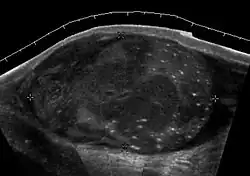

Seminoma is the most common tumor type in cryptorchid testes. The risk of developing a seminoma is increased in patients with cryptorchidism, even after orchiopexy. There is an increased incidence of malignancy developing in the contralateral testis too, hence sonography is sometimes used to screen for an occult tumor in the remaining testis. On US images, seminomas are generally uniformly hypoechoic, larger tumors may be more heterogeneous [Fig. 3]. Seminomas are usually confined by the tunica albuginea and rarely extend to peritesticular structures. Lymphatic spread to retroperitoneal lymph nodes and hematogenous metastases to lung, brain, or both are evident in about 25% of patients at the time of presentation.